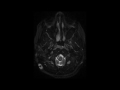

Intracranial Hypotension

This is a case of intracranial hypotension in an 18-year-old female following ventriculoperitoneal shunt placement. The first image through the supratentorial compartment demonstrates a slit-like appearance of the frontal horns of the lateral ventricles. There is a general fullness and partial effacement of the cerebral cortical sulci. More inferiorly, on the second image through the posterior cranial fossa, we see that the overall effacement of the extra-axial CSF spaces continues, and the fourth ventricle is completely effaced. On the third image with axial T2 weighting through the level of the foramen magnum, there is crowding of the foramen with descent of the cerebellar tonsils. The fourth image, a sagittal CISS sequence, demonstrates sagging of the brainstem and fullness of the pituitary gland. Inferior descent of the supratentorial structures is confirmed on the coronal T1-weighted sequence, image 5, where there is mild downward transtentorial herniation of the uncus bilaterally. The final image, a postcontrast sagittal T1-weighted sequence, redemonstrates brainstem sagging, cerebellar tonsillar crowding, and increased pachymeningeal thickening and enhancement. Intracranial hypotension classically presents as a positional headache relieved with recumbent positioning. The opening pressure at LP will be decreased. Bilateral subdural hygromas may also be visualized.